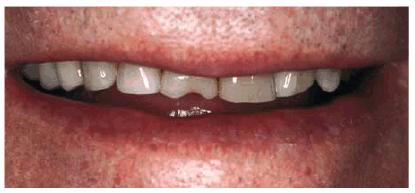

smile (Figur 323s1823d es 18-1A, and 18-1B). Decades ago, the full crown

Figur 323s1823d e 18-1A: This 21-year-old girl had chipped her anterior incisors when she was a teenager.

Figur 323s1823d e 18-1B: Cosmetic contouring was the most conservative treatment available and was performed in a less than 1-hour appointment.